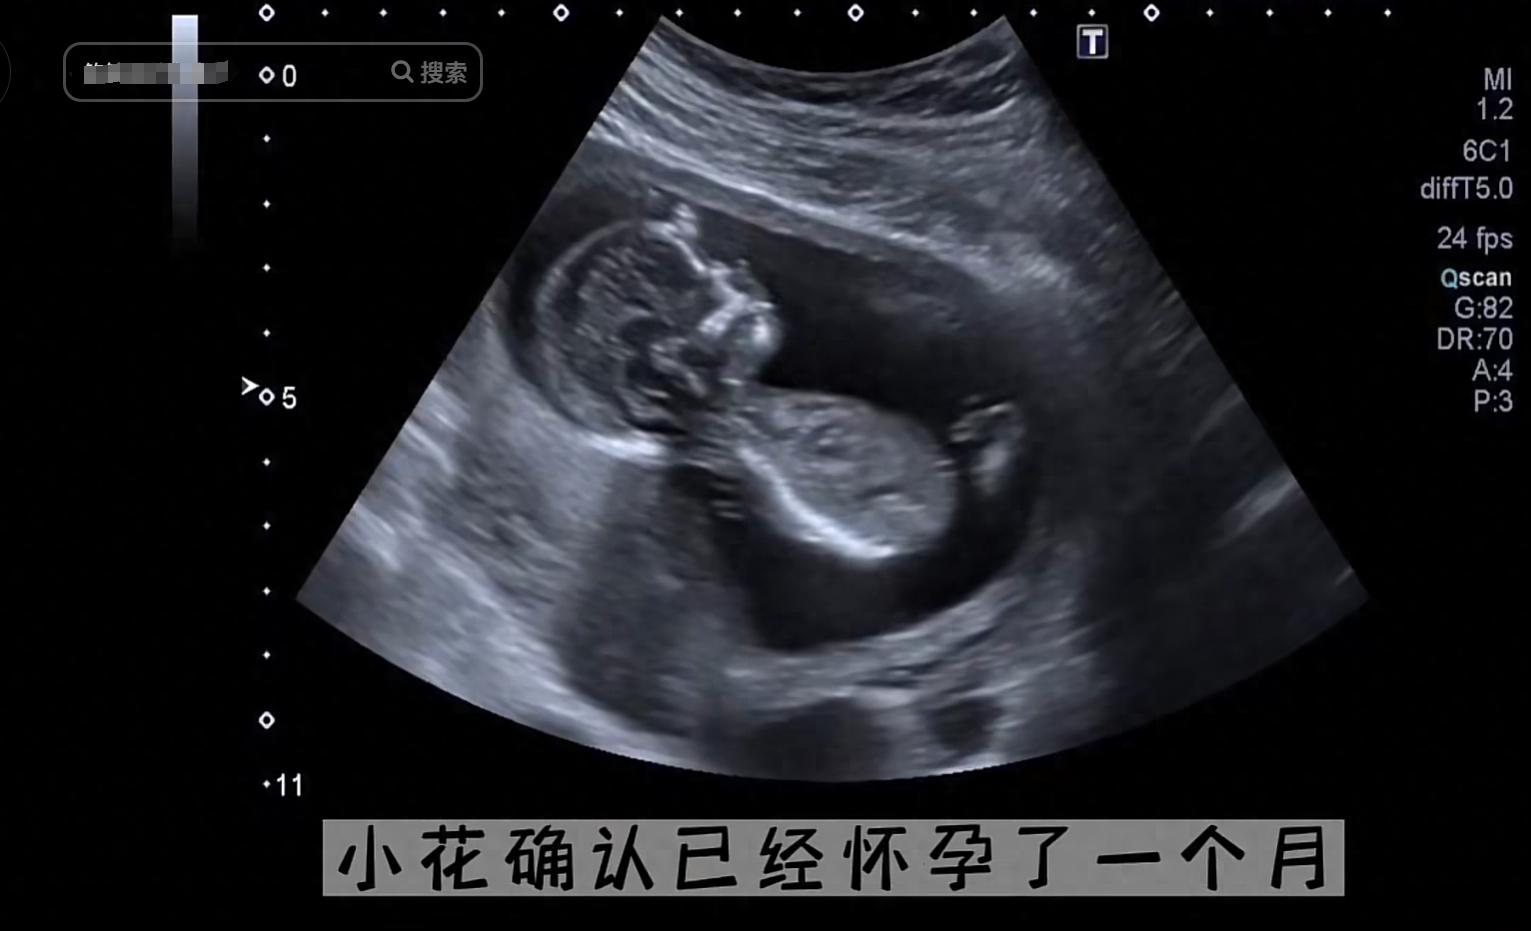

15歲的女孩小花上初二,她發現到自己該來月經的時候沒有來月經,而且隱隱覺得不太對勁,於是她悄悄進行了驗孕檢查,發現自己真的懷孕了,她不敢告訴媽媽,只偷偷的借了錢要去醫院去打胎,她以爲這樣子就能夠瞞天過海,把孩子打下來就能萬事大吉。